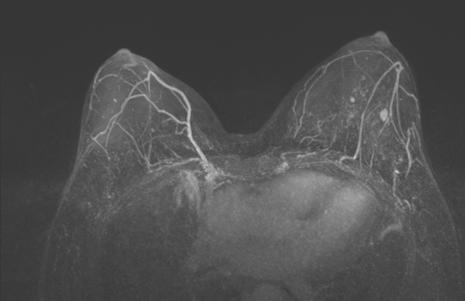

图3. 上图为治疗前,下图为治疗6周期后

治疗6个周期后,乳腺增强MRI显示靶病灶明显缩小,临床疗效评估为PR;腋窝靶病灶消失,临床疗效评估为CR。